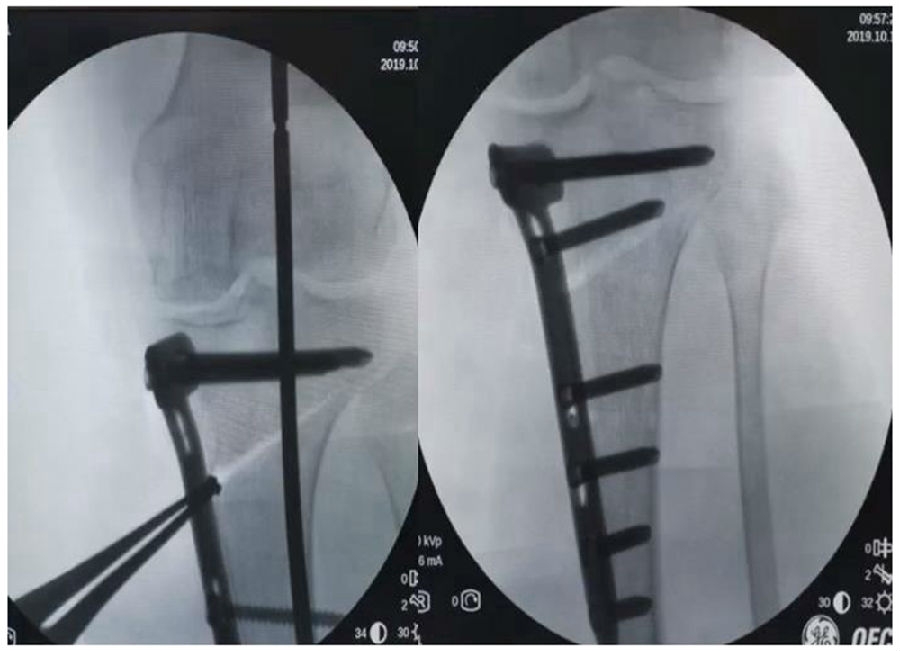

(2)Ⅱ型骨折

当出现Ⅱ型骨折时要特别注意,因为此时截骨的远端就是骨折的远端,近端只有上胫腓周围骨筋膜存在,所以相对来说Ⅱ型骨折并不稳定。

首先用拉力螺钉复位,调整好力线。然后做结构性植骨,延迟负重,所谓延迟负重就是延迟到外侧合页和上行截骨线处达到初始愈合,然后再让患者进行负重。如果不做结构植骨加延迟负重,就会出现一些非常严重的现象,如不愈合。

拉力钉复位,结构性植骨

左侧患者未植骨正常负重,术后4个月不愈合;右侧患者非结构性植骨过早负重,术后1年未愈合